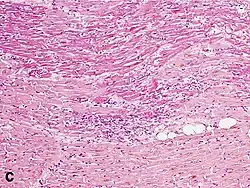

Under the microscope, myocardial infarction presents as a circumscribed area of ischemic, coagulative necrosis (cell death). On gross examination, the infarct is not identifiable within the first 12 hours.[22]

Although earlier changes can be discerned using electron microscopy, one of the earliest changes under a normal microscope are so-called wavy fibers.[23] Subsequently, the myocyte cytoplasm becomes more eosinophilic (pink) and the cells lose their transversal striations, with typical changes and eventually loss of the cell nucleus.[24] The interstitium at the margin of the infarcted area is initially infiltrated with neutrophils, then with lymphocytes and macrophages, who phagocytose ("eat") the myocyte debris. The necrotic area is surrounded and progressively invaded by granulation tissue, which will replace the infarct with a fibrous (collagenous) scar (which are typical steps in wound healing). The interstitial space (the space between cells outside of blood vessels) may be infiltrated with red blood cells.[22]

| Neutrophil infiltration | 12–24 h | 1–3 days | 5–7 days |

| Macrophages and lymphocytes | 3–5 days | 5–10 days (including 'siderophages') | 10 days to 2 months |